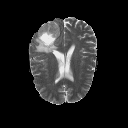

The goal of unsupervised anomaly segmentation (UAS) is to detect the pixel-level anomalies unseen during training. It is a promising field in the medical imaging community, e.g, we can use the model trained with only healthy data to segment the lesions of rare diseases. Existing methods are mainly based on Information Bottleneck, whose underlying principle is modeling the distribution of normal anatomy via learning to compress and recover the healthy data with a low-dimensional manifold, and then detecting lesions as the outlier from this learned distribution. However, this dimensionality reduction inevitably damages the localization information, which is especially essential for pixel-level anomaly detection. In this paper, to alleviate this issue, we introduce the semantic space of healthy anatomy in the process of modeling healthy-data distribution. More precisely, we view the couple of segmentation and synthesis as a special Autoencoder, and propose a novel cycle translation framework with a journey of 'image->semantic->image'. Experimental results on the BraTS and ISLES databases show that the proposed approach achieves significantly superior performance compared to several prior methods and segments the anomalies more accurately.